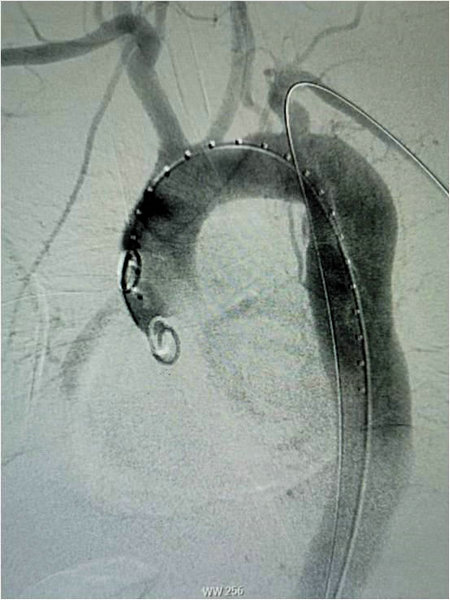

释放支架主体及分支并后扩分支支架:从右侧股动脉引入超硬导丝至升主动脉,沿着超硬导丝送入输送系统并上推至升主动脉,助手配合牵拉分支导丝,使分支支架进入左锁骨下动脉,并使支架窗口对准左侧椎动脉开口,经造影确认支架定位准确后,快速释放主体支架,助手配合牵拉导丝释放分支支架。撤出支架主体,由左侧股动脉导入8-80球囊扩张支架支架,沿左侧股动脉入金标导管至升主动脉,造影显示支架有效封堵夹层破口,无移位和内漏现象发生,左椎动脉与左锁骨下动脉血流通畅,手术圆满成功。